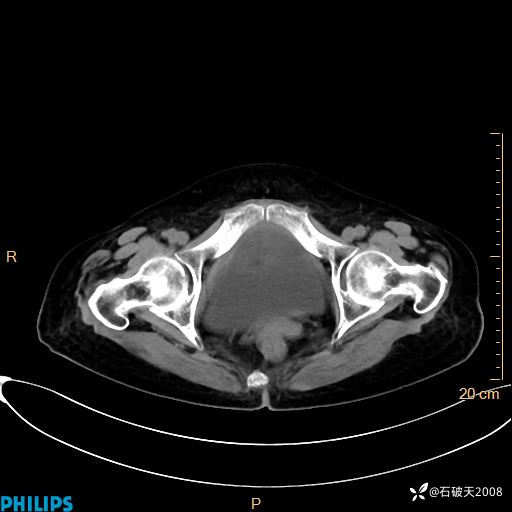

平扫

动脉期

MIP

静脉期